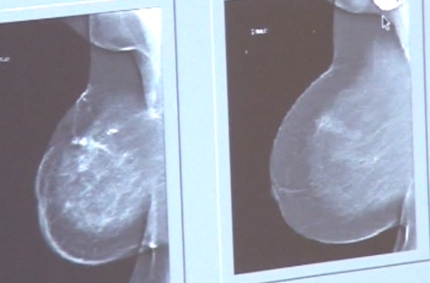

– O ważnej roli, jaką pełni profilaktyka zdrowotna przypominamy sobie zazwyczaj, kiedy jest już za późno na badania kontrolne i niezbędne okazuje się leczenie. Mammografia, czyli radiologiczne badanie piersi, to jedna z najbardziej skutecznych metod w diagnostyce wczesnych objawów raka piersi. Co więcej, mammografia jest badaniem bezpiecznym i wykonywanym przy użyciu minimalnej dawki promieniowania rentgenowskiego – przekonują organizatorzy akcji.